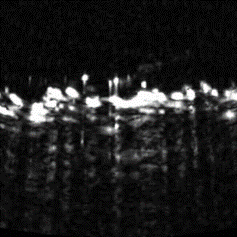

Cross sectional view

Surface(Depth) view

MAP